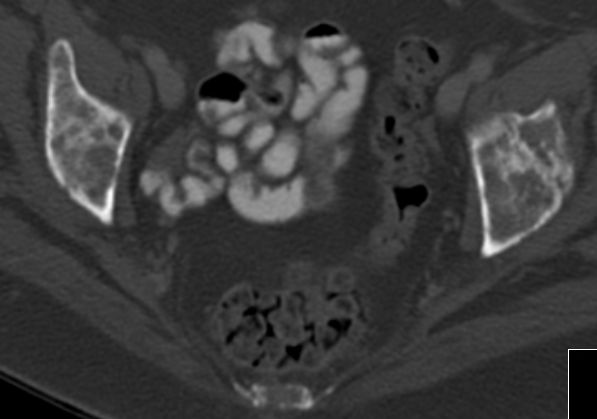

52-jährige Frau mit exulzeriertem, blutendem

Mammakarzinom T4b N3a M1. Metastasierung des Pfannendachs.![]() | ||||||||||